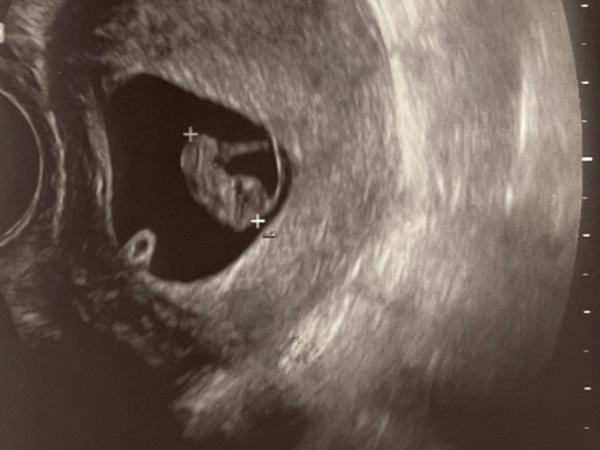

Genau 8+2 gestern. Drücke dir die Daumen :)

Bild zu